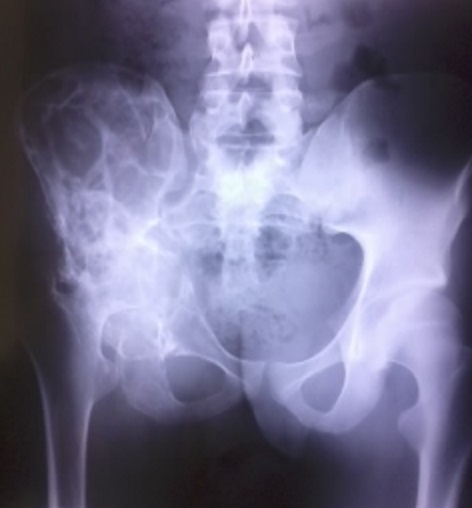

Os iliaque en nid d’abeille

L’hydatidose est une anthropozoonose due au développement de la forme larvaire du ténia Echinococcus granulosus chez l’homme. L’infestation humaine est accidentelle. Elle atteint le foie et le poumon dans 85 à 90 % des cas et l'os dans seulement 0.5 à 2 % des cas. Du fait de sa longue évolution, l'hydatidose osseuse est généralement découverte chez l'adulte. La douleur et la tuméfaction sont les principaux signes d'appel. Les tests immunologiques qualitatifs et quantitatifs sont d'un grand apport diagnostique mais ne sont positifs que dans 30 à 40 % des cas. Quel que soit son siège, l'hydatidose se traduit sur les radiographies par une ostéolyse lacunaire en "nid d'abeille" avec un cortical longtemps respecté. L'ostéocondensation est absente ou discrète sauf en cas de surinfection, absence de réaction périostée ou de reconstruction osseuse. La forme générale de l'os est conservée. Nous rapportons le cas d’un patient âgé de 20 ans, suivi pour douleur chronique de la hanche droite avec installation de boiterie. La radiographie standard faite objective une destruction de l’articulation coxo-fémorale avec des lésions multiples en nid d’abeille de l’os iliaque, et respect de la forme générale de l’os. Une biopsie osseuse faite revient en faveur d’un kyste hydatique intra-osseux sans signe de malignité. La sérologie hydatique est revenue positif avec un titre de 1/2560. Le patient est mis sous traitement médical à base d’Albendazole.